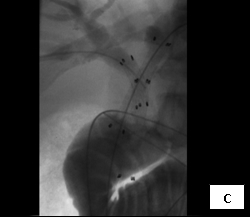

So, coming through a fresh percutaneous access on his right side (red arrow, image B) and through the drainage catheter already in his left hepatic duct (blue arrow, image B), I concurrently deployed stents across the obstructed confluence of the hepatic ducts and across the common bile duct. The effect of the treatment is evident by comparing images A and C: decompression of the dilated right and left hepatic ducts, relief of the critical obstruction of the common bile duct, and quick movement of copious amounts of the injected dye (which correlated with the movement of bile) into the duodenum.